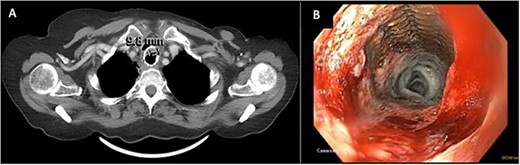

In April of 2022, the patient developed recurrent pneumonias, hemoptysis, and progressive dyspnea, raising concern of tumor invasion into the airway. Bronchoscopy confirmed a large tumor encompassing 2/3 of the airway, with evidence of stent erosion through the trachea (August 2022, Fig. 3). Laser debridement of the tumor was successfully performed.

Bronchoscopic evidence of tumor growth into the trachea with evidence of stent erosion (August 2022).